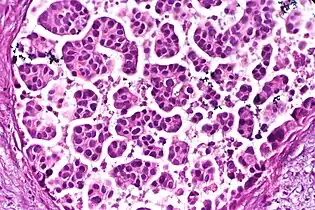

Acinar or tubular: Each acinus consists of cells that surround a lumen.

Cribriform: Solid with multiple clear spaces.